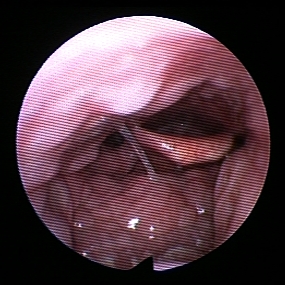

Bei Patienten mit einem habituellen Schnarchen oder mit einem Schlafapnoe-Syndrom, welche die cPAP-Maskenversorgung nicht wünschen oder nicht vertragen, kann geklärt werden, wo genau das Schnarchen entsteht. Dieses erfolgt durch eine Endoskopie im künstlichen Schlaf (Propofol-Somnoendoskopie), welche ambulant im Krankenhaus durchgeführt wird. Man geht dabei mit einem dünnen flexiblen Endoskop (Nasopharyngoskop) über die Nase in den Nasenrachen. Der Patient bekommt dann das Narkosemittel Propofol, womit ein künstlicher Schlaf eingeleitet wird. Im Regelfall fängt der Patient an zu schnarchen und man kann über das Endoskop beobachten welcher Mechanismus für das Schnarchen ursächlich ist. Bei der Endoskopie wird auch durch den Anästhesisten ein Esmarch-Handgriff durchgeführt. Dieser Handgriff (bekannt aus dem Erste-Hilfe-Kurs) bewirkt eine Vorverlagerung des Unterkiefers. Der endoskopierende HNO-Arzt sieht dann welchen Effekt dieser Handgriff auf die Engstellen und die Geräuschentstehung des Schnarchens hat. Somit kann der Erfolg einer Protrusionsschiene (eine der Therapieoptionen) abgeschätzt werden. Die Propofol-Somnoendoskopie ist ungefährlich und nicht schmerzhaft. Falls sie doch als unangenehm empfunden wird, kann die Nase auch lokal betäubt werden.

Meistens entsteht das Schnarchen durch Vibrationen im Bereich des Gaumensegels inklusive der Uvula (Zäpfchen) oder des Rachens (siehe Video). Aber auch Vibrationen im Bereich der Epiglottis (Kehldeckel) mit Ansaugphänomen oder im Bereich des zurückfallenden Zungengrundes werden beobachtet.

Typische velare Ronchopathie mit Vibrationen und Geräuschentstehung (leider ohne Ton) im Gaumensegelbereich.

Bitte auf das Bild klicken, um das Video zu laden. |